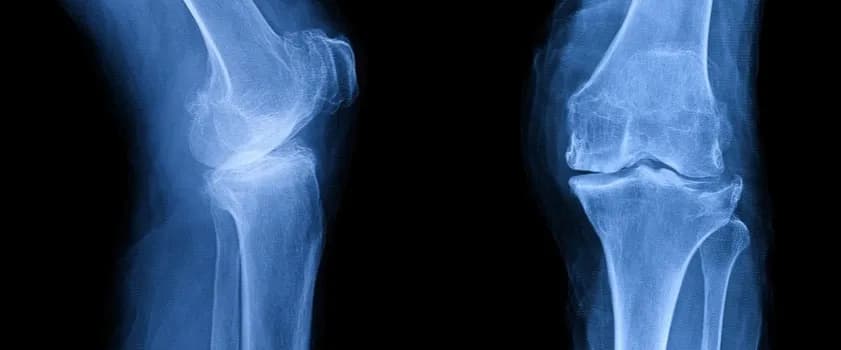

Tag jak poprawić stan przy osteofitozie